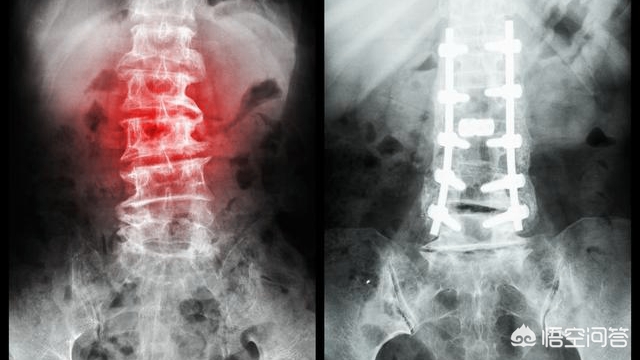

不论是手术治疗还是手法复位固定,都具有其优缺点。传统的手法复位方法,具有愈合快、疗程短、病痛少、收费标准低、无创,对很多普通家庭一般性骨折也是首选,但往往不能达到解剖复位,在治疗期间,石膏或夹板的固定将会给患者在日常活动中带来很大的不便,对患者的肢体功能和生活质量影响较大,同时也会延长复健的时间。手术治疗可以很清晰确定下进行骨折复位,而且可以达到更好的治疗效果,另外,手术治疗还可以通过内部固定的方式来达到固定目的,从而更快达到早期功能锻炼的目的。其相应的缺点在于有创,并且费用相对来说比较高昂。

总而言之,治疗骨科疾病时,都要把握住保守的正骨治疗方法优先,其次再来考虑采取手术治疗,不管哪种治疗方法,都是以患者的痊愈为宗旨。